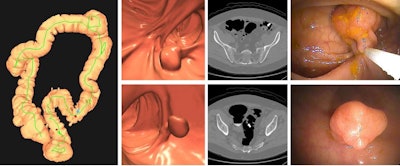

Images depict a positive CT colonography screening exam result in an asymptomatic 67-year-old man. 3D colon map from CT colonography (left image) shows the location of two sigmoid polyps that were detected (red dots). 3D endoluminal and confirmatory 2D transverse CT colonography images show a large 1.6-cm pedunculated polyp on top row (arrow) and a 9-mm pedunculated polyp in the distal sigmoid on the bottom row (arrow). Both polyps were confirmed and resected at optical colonoscopy performed the same day (right images), avoiding the need for a second bowel preparation. The larger polyp proved to be a tubulovillous adenoma (large advanced adenoma), whereas the smaller polyp was a nonadvanced tubular adenoma. Compare this level of information of a positive CT colonography screening test result with a positive multitarget stool DNA test result, for which no specific information is provided.Images depict a positive CT colonography screening exam result in an asymptomatic 67-year-old man. 3D colon map from CT colonography (left image) shows the location of two sigmoid polyps that were detected (red dots). 3D endoluminal and confirmatory 2D transverse CT colonography images show a large 1.6-cm pedunculated polyp on top row (arrow) and a 9-mm pedunculated polyp in the distal sigmoid on the bottom row (arrow). Both polyps were confirmed and resected at optical colonoscopy performed the same day (right images), avoiding the need for a second bowel preparation. The larger polyp proved to be a tubulovillous adenoma (large advanced adenoma), whereas the smaller polyp was a nonadvanced tubular adenoma. Compare this level of information of a positive CT colonography screening test result with a positive multitarget stool DNA test result, for which no specific information is provided.RSNA